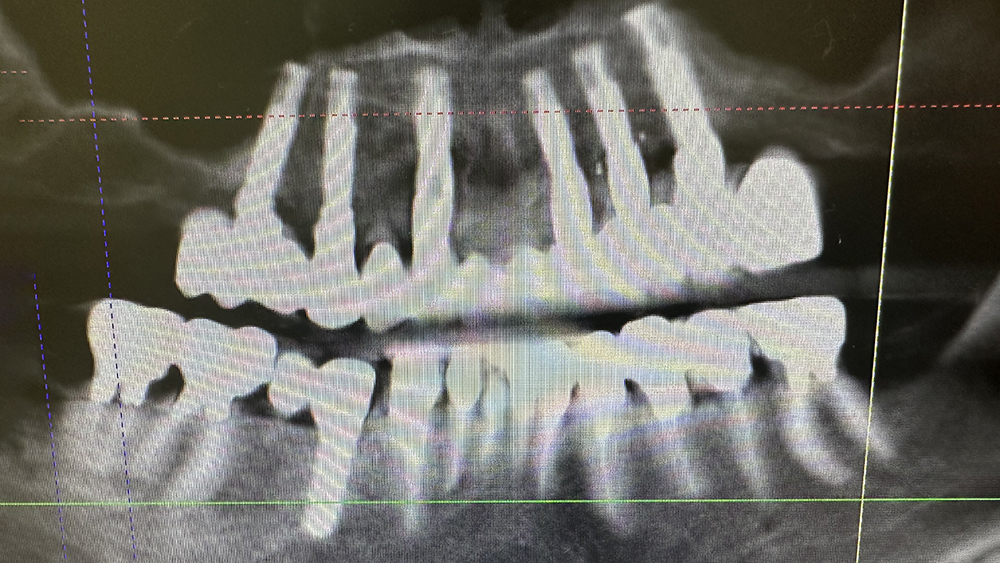

症例3

MHさん、84歳女性

非喫煙者

治療の期間・回数:約6か月

​治療の価格:約2,200,000円

治療内容:当院では平成5年から上あごの「オールオンX」を行っていますが、この方は最も古い患者さんです。

すでに21年経過しています。右下の歯が折れたため、12年前にオステムインプラントを1本追加しました。